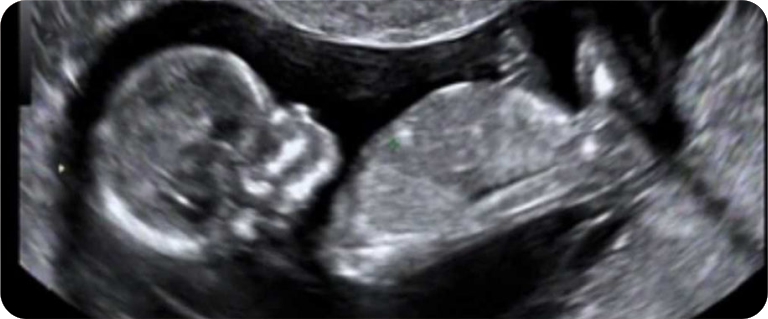

A ultrassonografia morfológica fetal de segundo trimestre é aquela feita entre 20 e 24 semanas de idade gestacional (ou no do inicio da 21ª até o final da 24ª semana) de gravidez. É um exame de ultrassonografia que consiste em fazer uma avaliação das estruturas de cada segmento do feto (cabeça, pescoço, coluna vertebral, tórax, abdômen, genitália externa e extremidades) e do liquido amniótico, cordão umbilical e placenta, com auxílio do Doppler colorido.

O Doppler colorido é um recurso utilizado para medir o fluxo sanguíneo em determinados vasos maternos e/ou fetais. Na ultrassonografia de segundo trimestre é feita a análise das artérias uterinas e da artéria umbilical.